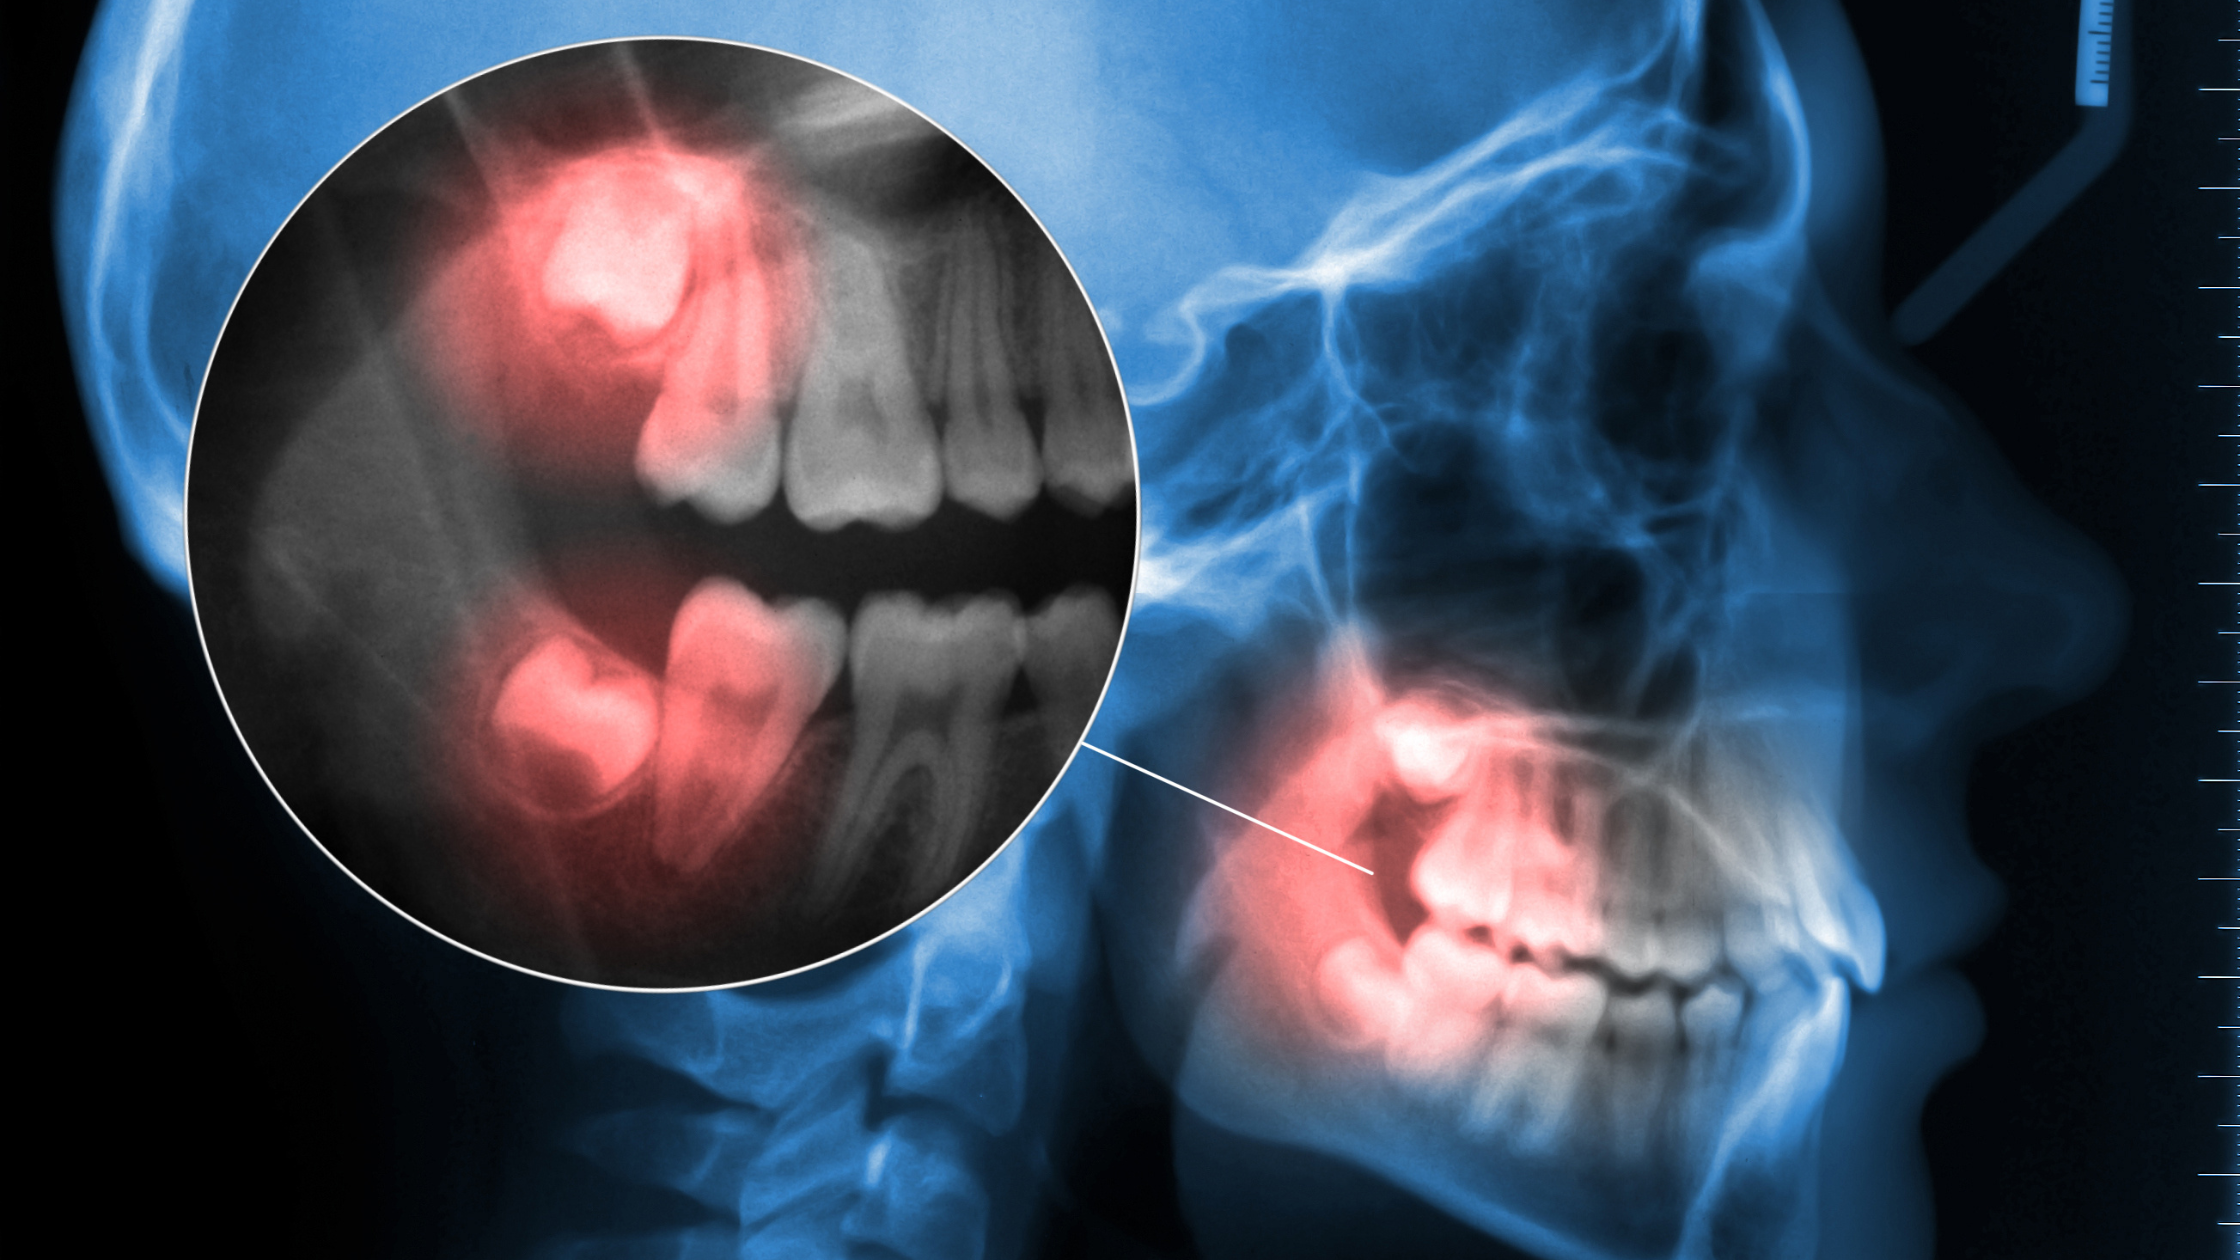

Two nerves in your lower jaw sit in close proximity to the roots of your lower wisdom teeth. These are the inferior alveolar nerve and the lingual nerve, and their location is one of the most important factors we assess before any extraction.

The inferior alveolar nerve runs through a canal inside your lower jawbone. It provides sensation to your lower teeth, lip, and chin. When wisdom tooth roots sit very close to this canal, or wrap around it, extractions carry a higher risk of nerve contact.

Traditional dental X-rays provide a two-dimensional view of your teeth and jaw. They can show that a wisdom tooth root is near the nerve canal, but they can’t show exactly how close, or in which direction the root curves.

Cone beam computed tomography (CBCT) imaging changes this entirely. CBCT creates detailed 3D images of your teeth, roots, nerves, and bone, showing us the exact spatial relationship between wisdom tooth roots and nerve canals from every angle.

When reviewing CBCT scans, we assess:

- The exact distance between the root tip and the nerve canal

- Whether roots are straight, curved, or hooked around the canal

- The position of the canal relative to the tooth roots

- Bone density surrounding the tooth